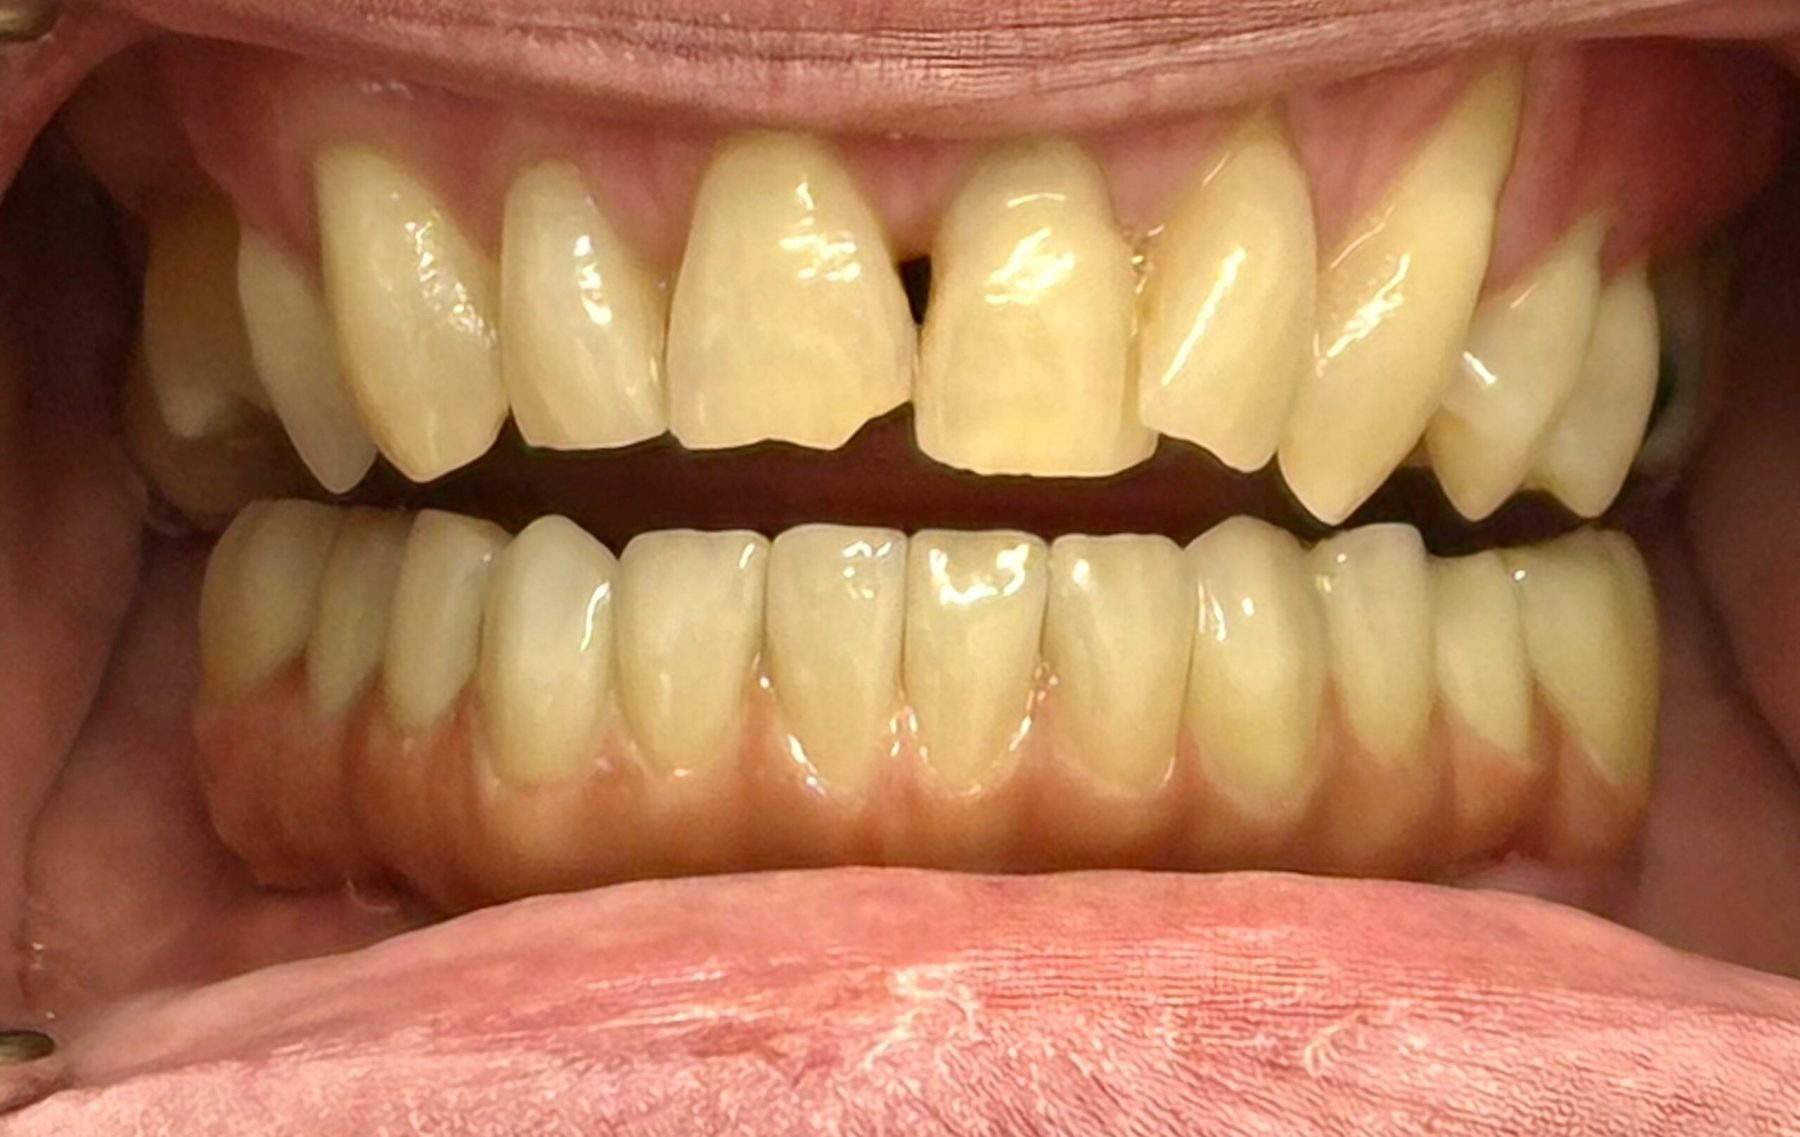

Full smile rehabilitation involving replacement of missing and failing teeth with implant-supported restorations, combined with aesthetic correction of existing dentition. The treatment was carefully planned to restore function, improve alignment, and achieve a balanced, natural-looking smile.

Implants were strategically placed to support long-term stability, with particular attention to soft tissue contours and emergence profiles to ensure seamless integration with the surrounding teeth. The final restoration was designed to enhance both aesthetics and bite function, delivering a confident and harmonious result.

This case demonstrates a comprehensive approach to implant and restorative dentistry, combining surgical precision with advanced prosthetic design to achieve predictable, long-term outcomes.

Immediate implant placement with simultaneous bone augmentation and connective tissue grafting. The case will be completed with crown lengthening, veneer replacement, and soft tissue optimisation to achieve ideal emergence profiles.